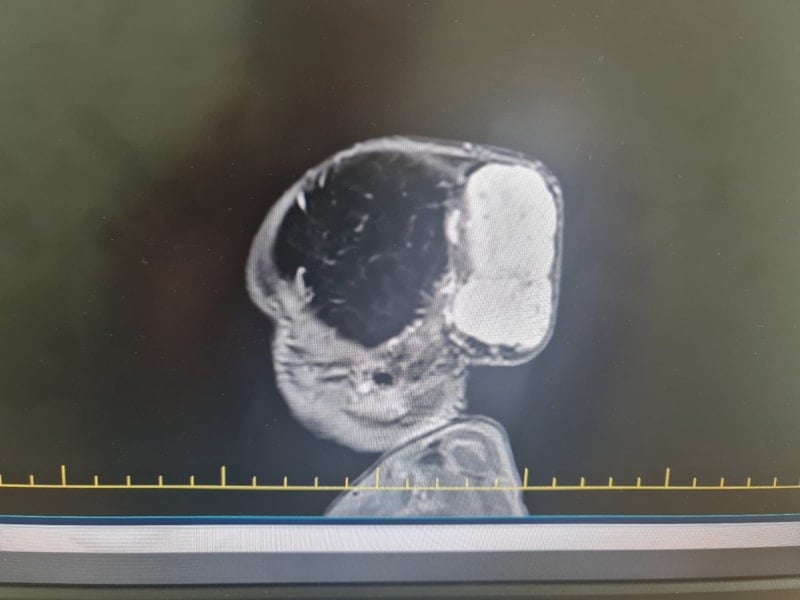

Gaziantep’te Yalçın Enes ve Tuğba Yalçın çiftinin 1,5 yaşındaki çocukları Talha, kafasında büyük bir kitle ile dünyaya geldi. Hastanede yapılan tetkiklerde, boyutları 7 x 6,5 x 4 santimetre olan ve dünyada nadir görülen bir tümör olduğu tespit edildi.

Gaziantep Şehir Hastanesi Beyin ve Sinir Cerrahisi Kliniği ekibi tarafından gerçekleştirilen ameliyat, toplam 4 saat sürdü. Operasyonda, girişimsel radyoloji ekibinin önceden yaptığı embolizasyon işlemi ile tümörün kanlanması azaltıldı. Ardından plastik cerrahi ve beyin cerrahisi ekibinin ortak çalışmasıyla tümör başarıyla çıkarıldı.

Hastamız Talha bebek, başında dev bir kitle ile doğdu. Tümör yoğun damarlanmış ve beyin dokusuna baskı yapıyordu. Bu nedenle ameliyat stratejimizi yeniden kurduk ve multidisipliner bir yaklaşım uyguladık. Ameliyat başarıyla tamamlandı ve Talha bebeğimiz sağlığına kavuştu.

Kitlenin hızlı büyümesi, kafatası kemiklerine invazyonu ve agresif yapısı nedeniyle ameliyat zorluydu. Ekibimiz multidisipliner bir yaklaşımla süreci başarıyla tamamladı. Anestezi ve yoğun bakım ekiplerimiz de operasyon sürecinde büyük destek verdiler.